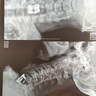

Спасибо, хирургам, нейрохирургии √2,за приведённую операцию по удалению межпозвоночной грыжи, быстро красиво профессиона...льно .Еспенбетов.Е.Б.,Тян.В.К.,Макежанов.Е.С,.Тулбелбаев Е.К,.Алиев.М.А.

Хочу поблагодарить врачей отделения реанимации, нейрохирургии, а именно Заведующего отделения анестезиологии и реанимат...ологии Есенай Бахытжановича, нейрохирургии Тян Валерий Кирилловича, лечащего врача Макежанова Ербола Сапарбековича, хирурга, который делал мне операцию на голову Тубелбаева Ерлана Кенжебековича, анестезиолога Алиева Абилхана, ассистента Куйкасова Газиза Болатовича и всем врачам, медсёстрам дежурившим в тот день, 8 июня 2018г., в ГКБ Калкаман 7, а также скорую бригаду за оперативную и слаженную работу, чуткость и профессионализм, ведь вы спасли мне жизнь, после полученных страшнейших травм головы и трещины мозга от удара машины, повлёкших за собой кому. Без них, моя жизнь оборвалась бы уже давно! Они все сделали для меня! Нет слов, только слезы благодарности! Спасибо огромное, за Ваш труд, за Вашу непоколебимую стойкость в трудных ситуациях, за отзывчивость! Низкий поклон Вам, и самые теплые слова благодарности!